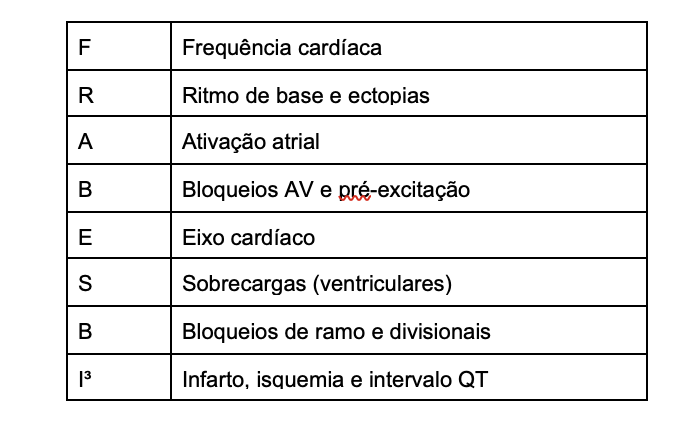

Tabela 1: A composição do acrônimo FRABESBI³

Tabela 1: A composição do acrônimo FRABESBI³

Tabela 1: A composição do acrônimo FRABESBI³

Tabela 1: A composição do acrônimo FRABESBI³ Figura 2: Ritmo sinusal alternando com ritmo de fibrilação atrial. A análise do ritmo é a segunda etapa na interpretação dos achados do traçado.